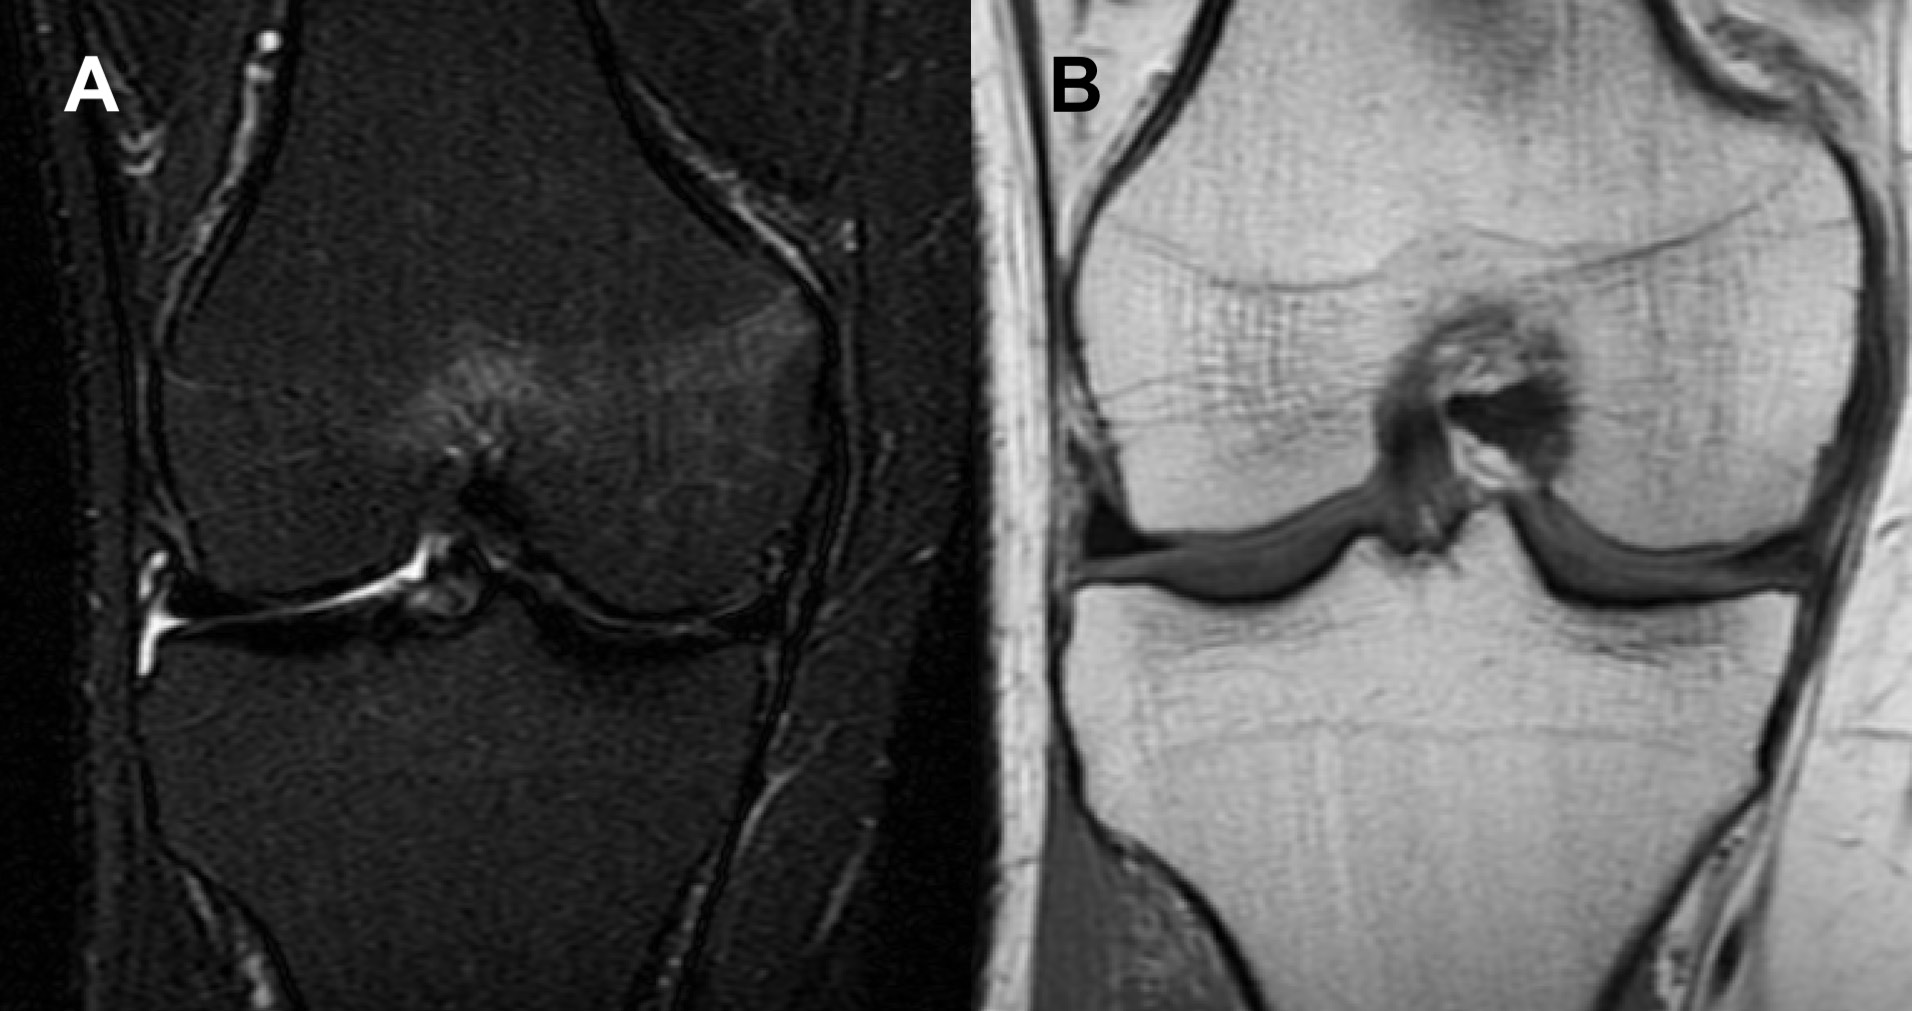

The symptoms subsided completely after approx. 8 weeks of nonoperative treatment. A follow-up MRI scan of the same knee was performed 10 weeks after the first appointment, and showed remission of the radiological findings in the MFC and medial aspect of the intercondylar region (Figure 2). The next follow-up MRI, which was performed 5 months after the first appointment, showed complete resolution of the bony and soft tissue edema (Figure 3). There were no adverse or unanticipated events.

Fig. 2. Follow-up magnetic resonance imaging (MRI) coronal view of the right knee (Case 1) performed after the resolution of symptoms. The signal in the medial femoral condyle in both (A) short tau inversion recovery (STIR) fast spin echo (FSE) and (B) proton density (PD) sequences is almost normal. It is noteworthy that there is no visible soft tissue edema.

Fig. 3. Second follow-up magnetic resonance imaging (MRI) coronal view of the right knee (Case 1). The signal in the medial femoral condyle in both (A) short tau inversion recovery (STIR) fast spin echo (FSE) and (B) proton density (PD) sequences is normal